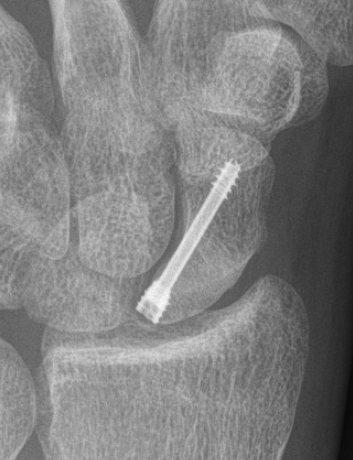

Scaphoid waist fracture 1 mm displaced

Scaphoid fracture with significant displacement

Scaphoid proximal pole fracture